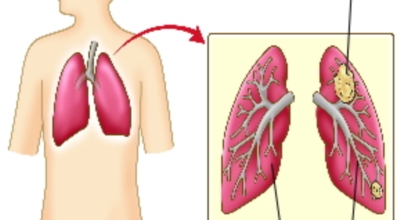

폐에 발생된 악성 종양을 말하며 오랜 기간 흡연해온 남성들에서 발병률이 높고 최근 들어 가지가지 환경적인 요인의 영향과 간접흡연으로 흡연하지 않는 여성에서도 많이 발생하고 있어요. 증상을 느껴 병원을 찾았을 때는 수술하기 늦은 경우가 많아 사망하는 비율이 매우 높은 암입니다. 폐 자체에서 생기거나 다른 장기에서 발생된 암이 폐로 전이되어 나타나기도 하고 특별한 초기 증상이 없는 경우가 많다고 하며 암이 진행된 후에도 일반적인 감기 증상인 기침과 가래 외의 특이 증상이 나타나지않아 증상만으로는 진단이 쉽지 않아요.

폐암의 초기증상 중에는 흉통이 있어요. 위치에 따라 요통으로도 진행이 되기도 하는데요 흉통이 발생하는 경우는 폐의 가장자리에 폐암이 발생할 때 나타나게됩니다. 흉막에 암이 인접해 위치하게 되면 바늘로 콕콕 찌르는 듯한 흉통을 느끼게 되며 폐암이 갈비뼈나 다른 부위로도 전이될 경우에도 흉통이 발생하고 요통으로도 발전 할 수 있어요.

폐암은 3기 이상인 말기에 발견되는 경우가 대개라 예전에는 폐암 판정을 받으면 곧 사망이라고 부르는 말까지 있답니다. 하지만 요즘엔 의료기술이 발달하여 폐암 5년 생존율은 70%가 넘고 있어요. 무엇보다 주기적인 건강검진으로 인해서 폐암을 조기에 발견한 경우가 많아서라고 볼 수 있어요. 세세히 살펴보면 인산화효소 변이 폐암 환자의 경우 5년, 상피세포 성장인자 수용체 변이 폐암 환자의 경우 1년~3년의 생존율을 보인다고 해요. 하지만 요즘도 폐암을 3~4기에서 확진 받는 경우가 많다고 해요.